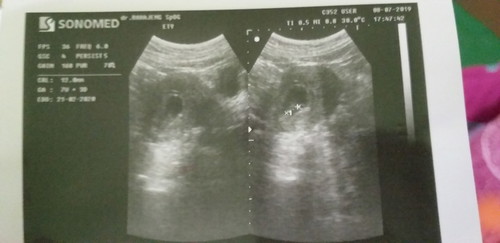

7weeks

Ini hasil usg barusan Setelah usg hasil ny 7 weeks,tapi klo hitung perkiraan bidan lewat HPHT sdh 8 weeks Janin sudah terlihat,walopun msh kecil..tapi detak jantung blm trdengar Dsn adakah yg alami hal sama Share ny bund

Jika usg perut, biasanya terdengar di 8-9minggu... Tapi umumnya jika sdh terlihat baby, sdh bisa dicek detak jantungnya... saran saya, coba cek usg transvaginal... Usg transvaginal itu sejak 5 minggu sdh bisa deteksi detak jantung